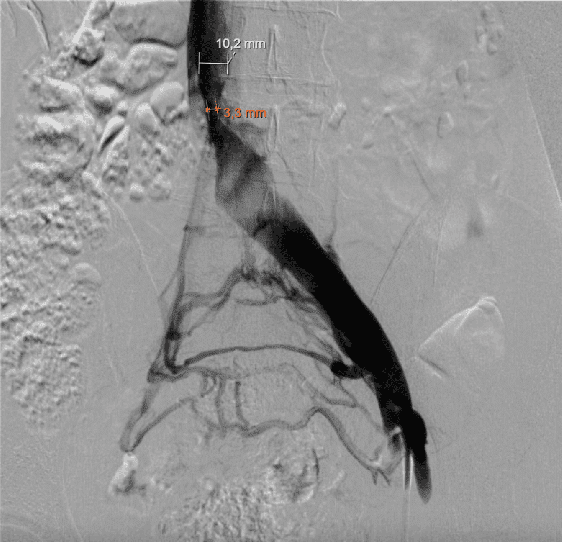

Resim. Venöz stent

Bu tedaviler ile üstteki atardamarın alttaki toplardamarı şıkıştırması önlemek ve bası bulgularını ortadan kaldırılmak amaçlanmaktadır.